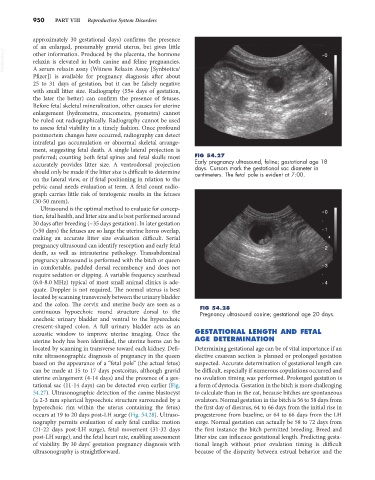

preferred; counting both fetal spines and fetal skulls most FIG 54.27

accurately provides litter size. A ventrodorsal projection Early pregnancy ultrasound, feline; gestational age 18

days. Cursors mark the gestational sac diameter in

should only be made if the litter size is difficult to determine centimeters. The fetal pole is evident at 7:00.

tational sac (11-14 days) can be detected even earlier (Fig. a form of dystocia. Gestation in the bitch is more challenging

54.27). Ultrasonographic detection of the canine blastocyst to calculate than in the cat, because bitches are spontaneous